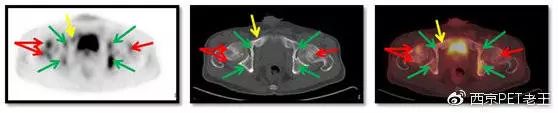

红色箭头:股骨头转移;绿色:髋臼转移;黄色:耻骨转移

我们又发现了这么多的骨转移病变,那原发病灶究竟在哪里呢?我们仔细寻找,在左肺上叶发现了一个空洞样病变,边缘见细毛刺及胸膜牵拉征,呈葡萄糖代谢异常增高,我们考虑为恶性病变(肺癌?),如下图:

左肺上叶发现了一个空洞样病变(红色)